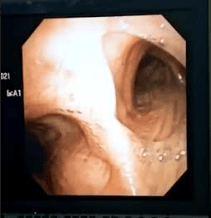

Se realiza fibrobroncoscopia flexible Se evidencia mucosa endobronquial sin lesiones, ni cambios de coloración (figura 4), en el cultivo del lavado bronquial reporta Klebsiella pneumoniae y Streptococcus ( figura 5) y en el bloque celular actinomicosis así como lo muestra la figura 6.